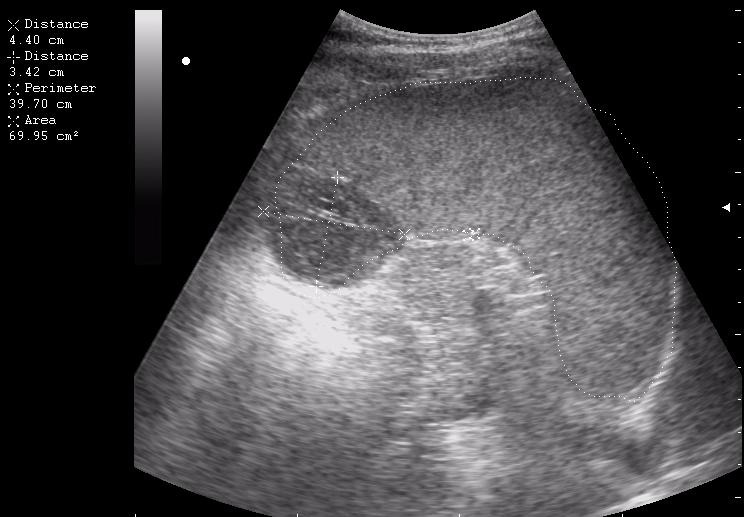

наезд большой черной Прады на маленькую (13кг) 5-летнюю девочку.

получает Медаксон, рабочая версия - изменение желчного пузыря вследствии травмы (шепотом - рекомендация хирургу сменить антибиотик)